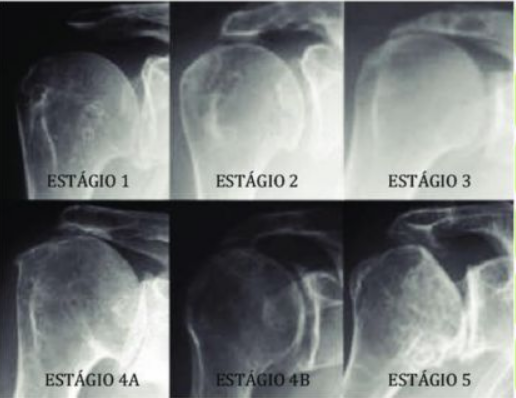

A classificação de Hamada para ruptura maciça do manguito rotador divide as características radiográficas das rupturas extensas do manguito rotador em V graus diferentes. Posteriormente Walch subdividiu o grau 4 em dois subtipos.

Tipo I: Distância acromioumeral (DAH) menor que 6mm.

Tipo II: Igual à 5mm ou menos

Tipo III: Acetabularização do acrômio

Tipo IV: Tipo III + diminuição do espaço glenoumeral

A - osteoartrite glenoumeral sem acetabulização, intervalo acromioumeral <7mm

B - osteoartrite glenoumeral com acetabulização, intervalo acromioumeral ≤5mm

Tipo V: Colapso da cabeça umeral com artropatia do manguito rotador.